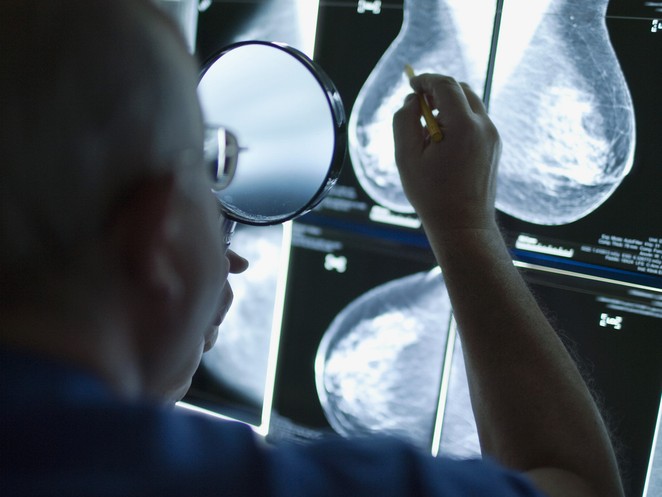

«Die Schweiz ist in der Gendermedizin das Schlusslicht»

Gendermedizinerin klagt an: Der Mann soll nicht mehr das Mass in der Forschung sein